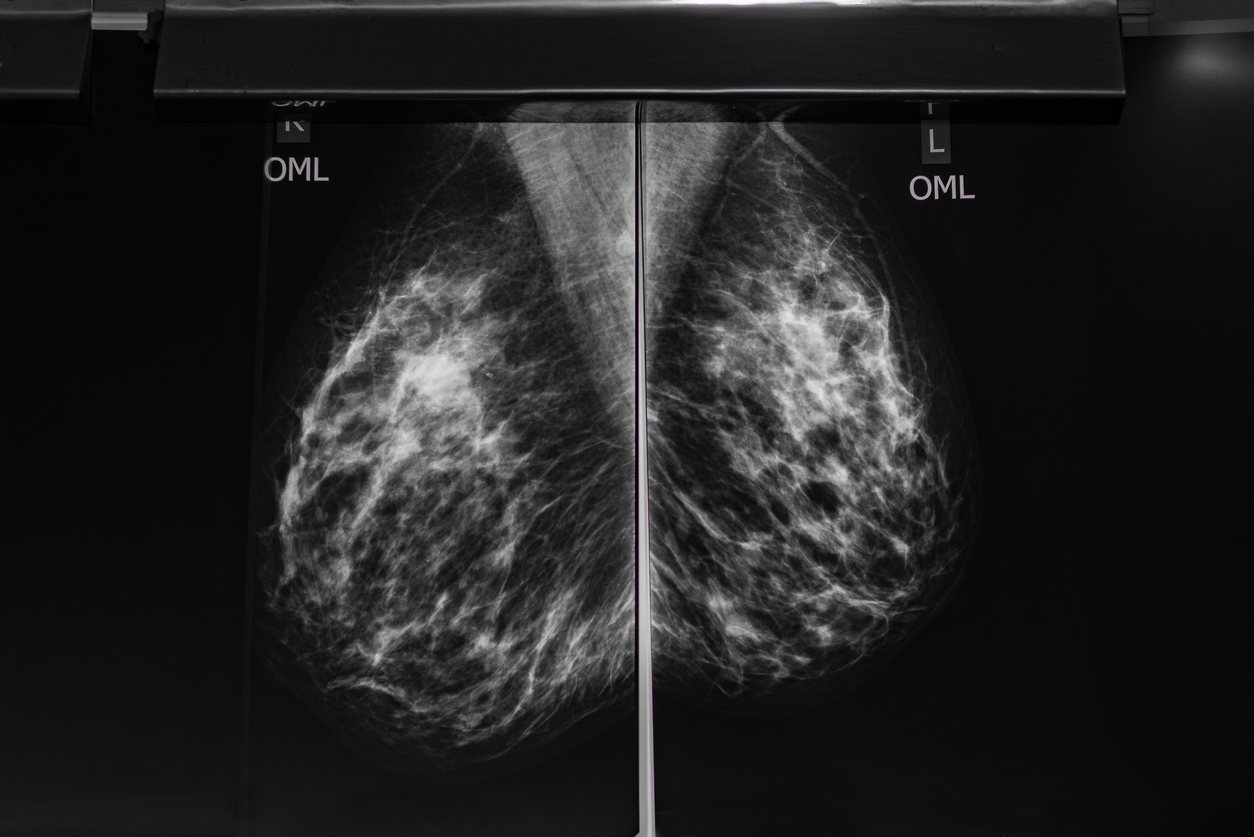

Breast density refers to the composition of breast tissue as seen on a mammogram. It does not describe how breasts feel during a physical exam but rather how different tissues appear on imaging.

Dense tissue includes milk glands, ducts, and supportive connective tissue. On a mammogram, dense tissue appears white. Breast density refers to the relative amount of these tissues present in the breast. Imaging determines breast density, not how the breasts look or feel.

Both dense tissue and tumors show up white on mammogram images. Because they appear similar in color, dense tissue can sometimes make it more difficult for radiologists to detect abnormalities.

A common analogy doctors use is that finding cancer in dense tissue is like trying to spot a snowball in a snowstorm; similar colors make subtle differences harder to see.